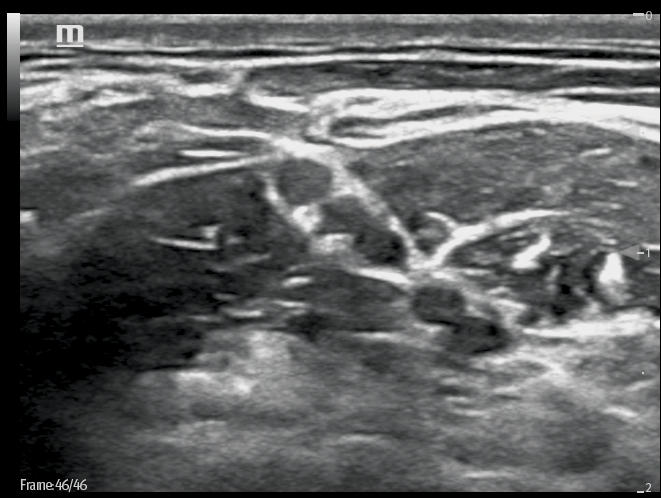

Ultrasound Reimagined

Advanced Technologies

Clinical Certainty Within Reach